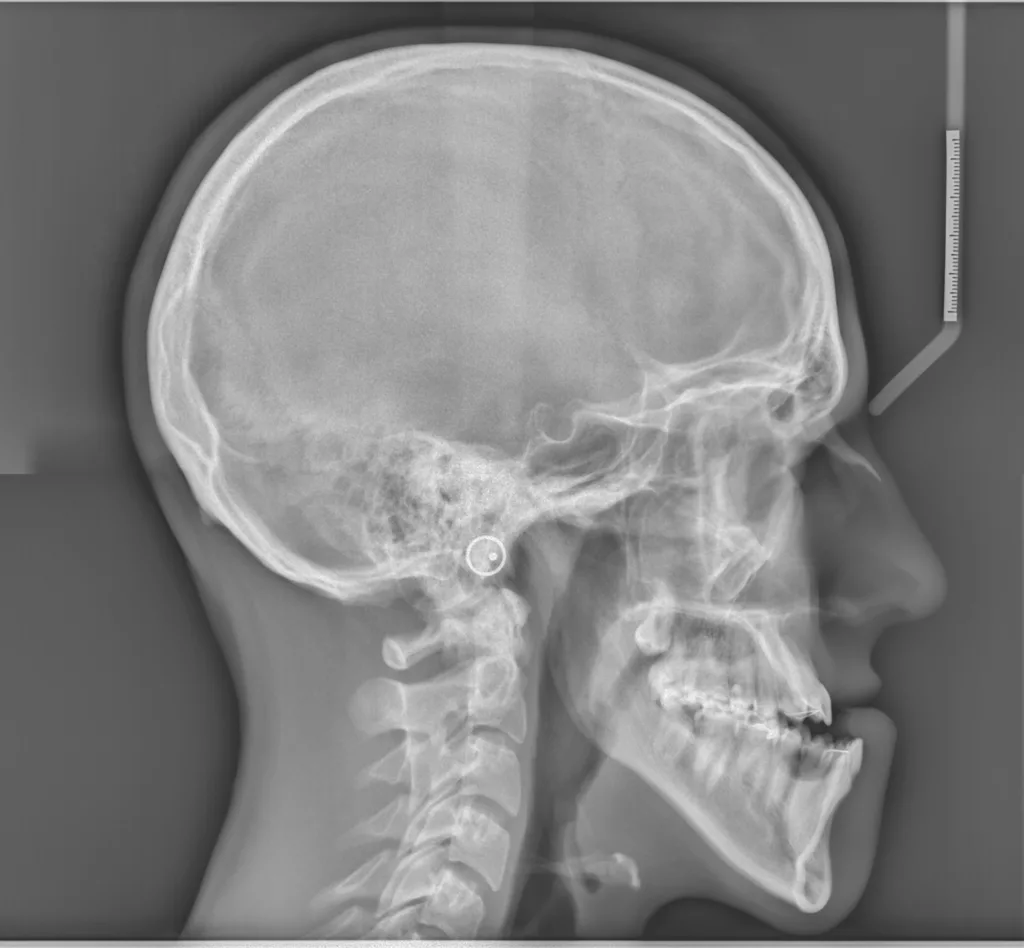

Parmi les examens radiographiques nécessaires, les radiographies de profil et de face correctement orientées et contenant l’ensemble de la tête (sommet du crâne inclus) sont particulièrement importantes. Ces radiographies correctement effectuées permettent d’établir une véritable cartographie du squelette du patient et en conséquence de comprendre sa malformation. Cette analyse cartographique du squelette a pour nom « céphalométrie ». De nombreux types d’analyses céphalométriques existent et sont utilisées selon les pays et universités. Parmi elles, l’analyse céphalométrique architecturale et structurale de Jean Delaire tient une place particulière.

L’Analyse Céphalométrique architecturale et structurale de Jean Delaire

L’analyse céphalométrique architecturale crânio-faciale de Jean Delaire, à la différence des autres méthodes d’analyse qui sont principalement basées sur des moyennes statistiques définissant ce qui est « normal » et ce qui est « anormal » (c’est à dire pathologique) est basée sur la notion d’équilibre ou de déséquilibre architectural du squelette crânio-facial propre à chaque individu en tenant compte des principaux appareils anatomiques à son contact et des principales fonctions qui interfèrent avec lui. « A l’état d’équilibre, tous les éléments de l’extrémité céphalique ; squelette et tissus mous sont et fonctionnent en parfait équilibre mutuel ».

Pour chaque individu, l’analyse architecturale crânio-faciale de Jean Delaire permet de déterminer « l’équilibre » squelettique idéal qui lui est propre c’est-à-dire « sa normalité » et de constater, s’il existe, l’état de «déséquilibre » dans lequel il se trouve, c’est-à-dire l’état « pathologique » dans lequel il se trouve en tenant compte de son âge, de ses antécédents personnels ou familiaux, de son état fonctionnel ou dysfonctionnel, de l’existence d’éventuelles pathologies associées.

Pour chaque patient étudié l’analyse céphalométrique de Jean Delaire permet de :

- Connaître et de quantifier le morphotype qui lui est propre

- Analyser la situation d’équilibre (la normalité) ou de déséquilibre (la situation pathologique) dans laquelle se trouve l’ensemble de son extrémité céphalique ; crâne, massif facial et rachis cervical (analyse architecturale),

- Déterminer la participation respective de chaque élément anatomique dans la malformation ; maxillaire, mandibule, os basal, os alvéolaire, dents (analyse orthognathique et dentaire),

- Evaluer l’anomalie de position de chacune des pièces et unités anatomiques et de connaitre la position qu’elles auraient dû avoir en l’absence de pathologie guidant ainsi au mieux le chirurgien dans son plan de traitement chirurgical (analyse topographique)

L’analyse architecturale est complétée par l’analyse structurale. Pour chaque patient elle consiste à examiner attentivement tous la « structure » de l’extrémité céphalique c’est dire l’anatomie de chacune des pièces squelettiques et des parties molles qui la compose pour mieux comprendre le mécanisme d’installation et d’entretien de la dysmorphose. En association avec l’analyse architecturale elle permet de poser le diagnostic le plus précis afin de choisir le meilleur traitement chirurgical et orthodontique.